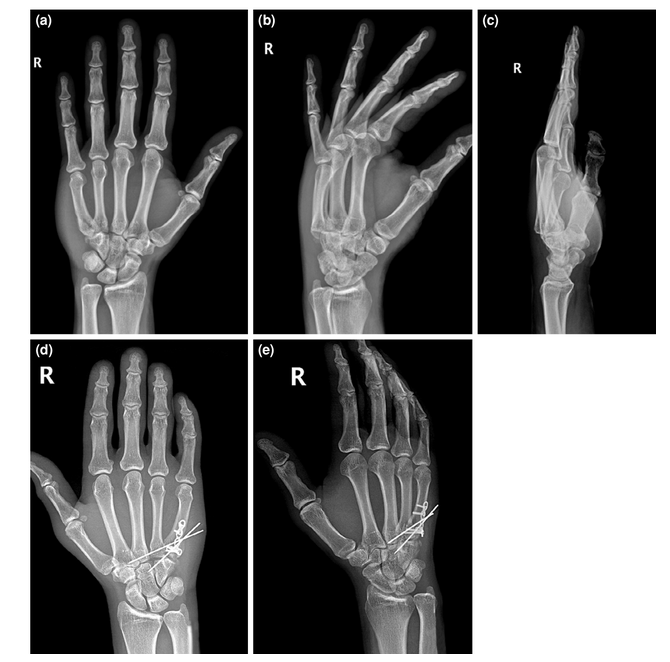

手术患者术前和术后的x线图像。(a)掌骨级联线AP x线。这些线沿着掌骨的轴线画;绿色表示解剖性,红色表示脱位,因为它不与其他关节相交。(b)术前斜位x线片。

手术治疗患者的术前和术后影像;钢板固定的一个例子。(a-c)术前AP、斜位和侧位x线图像。(d-f)术后AP、斜位和侧位x线图像。

手术治疗患者的术前和术后影像;一个附加关节桥接k线钢板固定的例子。(a-c)术前AP、斜位和侧位x线图像。(d, e)术后AP和斜位x线图像。